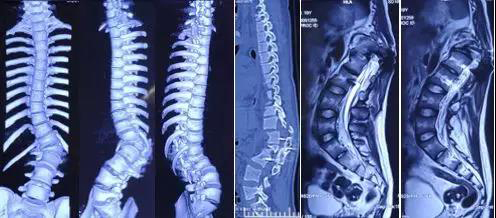

图1 患者术前3D-CT及MRI显示T11-L2多发骨折并脊髓受压,脊柱侧凸矫形术后内固定物存留。

胸11-腰2多发脊柱骨折并脊髓损伤、脑挫裂伤、额骨多发骨折、硬膜外血肿(左额部)、硬膜下血肿(右顶部)、多发肋骨骨折(右侧5-11)、创伤性湿肺,双侧血气胸,右侧肩胛骨骨折、脊柱侧弯矫形术后内固定存留。

患者10年前因脊柱侧弯在外院行脊柱侧后凸矫形术(胸12-腰2节段固定)。本次骨折累及矫形固定节段,导致患者病情复杂,治疗难度极大,治疗难点主要有以下几方面:

患者目前仍然存在脊柱侧弯,椎弓根定位困难,增加了植入椎弓根螺钉的难度。